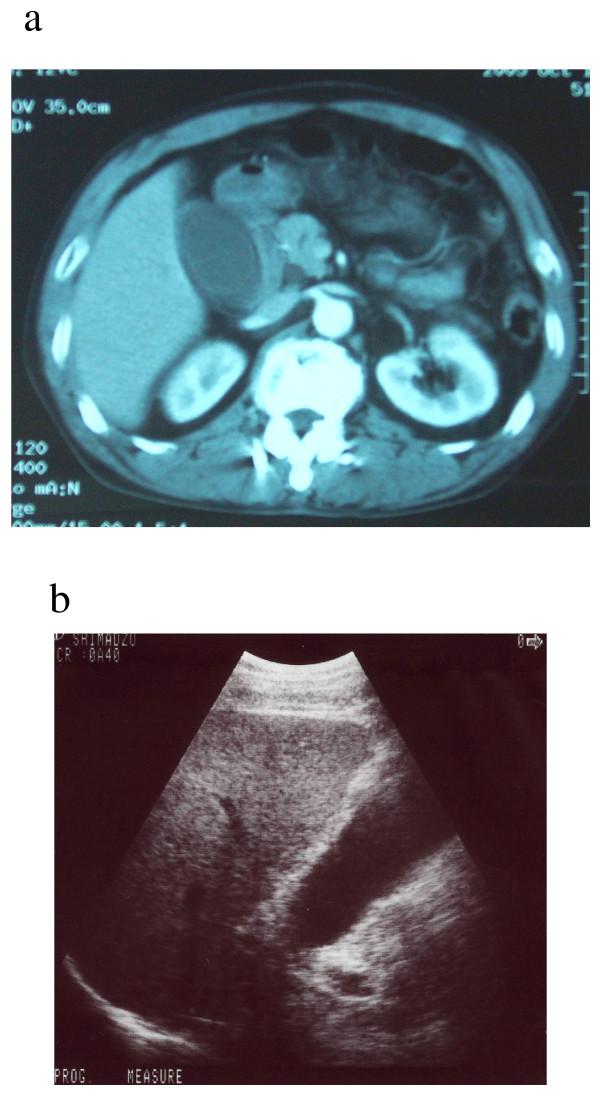

A 56-year-old man with carcinoma of the ampulla of Vater presented with spontaneous gallbladder perforation and localized bile peritonitis. He complained of right upper abdominal pain, and laparotomy revealed perforation of the gallbladder with no gallstones. Postoperative upper gastrointestinal endoscopy demonstrated a slightly enlarged duodenal papilla, and biopsy revealed adenocarcinoma of the ampulla. Pylorus-preserving pancreaticoduodenectomy was performed subsequently.

病例介绍